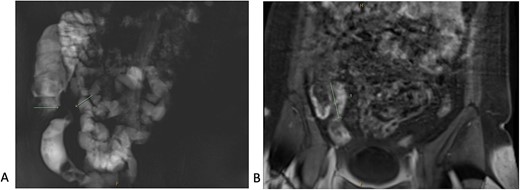

A 34-year-old female presented with colicky episodic abdominal pain and symptoms suggestive of subacute small bowel obstruction in the setting of known stricturing CD. Her symptoms were poorly controlled on multiple medications—Azathioprine, Mesalazine, Adalimumab and Budesonide. She had no previous history of abdominal surgery or gynaecological pathology. She had twice undergone endoscopic balloon dilatation of a terminal ileal stricture with short-lived symptomatic relief. Contrast-enhanced computed tomography (CT) of the abdomen and pelvis showed a short segment of acute inflammation of the terminal ileum (Fig. 1) and an incidental right adnexal cyst. Pelvic ultrasonography was normal. Magnetic resonance enterography confirmed stricturing CD with two segments of inflammation of the terminal ileum (lengths of 5 and 3.8 cm) approximately 5 cm from the ileocaecal valve (Fig. 2).

Computed tomography scan (portal venous phase post intravenous contrast) showing a short segment of thickened, enhancing terminal ileum consistent with terminal ileitis of CD.